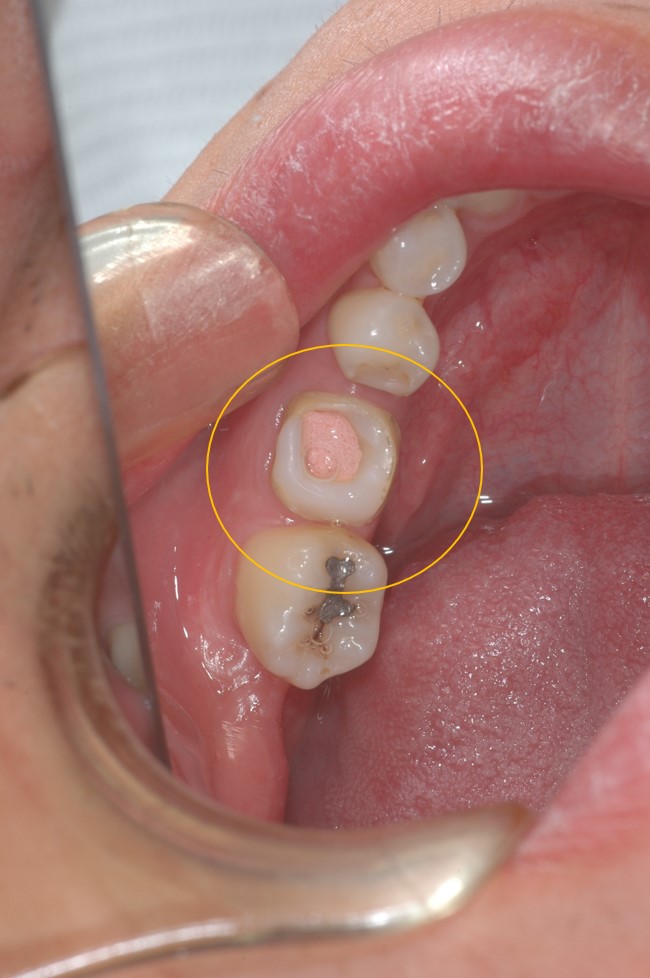

← 174.歯の移植手術(親知らず)